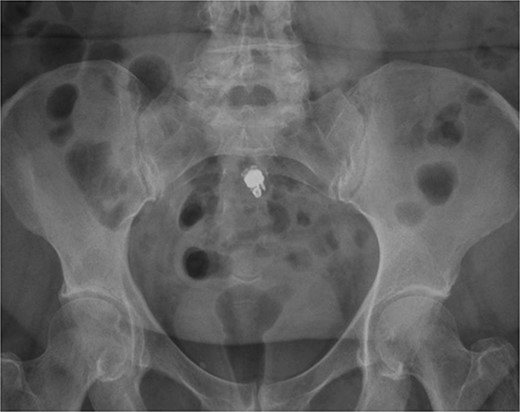

A 73-year-old male with a history of hypertension and CD presented to an outside facility in September 2022 with an ileal stricture and microperforation in the setting of ileitis. The patient underwent exploratory laparotomy for resection of the involved segment with reanastomosis. Pathology was positive for adenocarcinoma in a field of high-grade dysplasia and inflammatory changes consistent with Crohn’s. Two months later, the patient underwent VCE with an outside gastroenterologist. The capsule was retained at the distal ileum. Two weeks later, a colonoscopy revealed a stricture in the terminal ileum that could not be traversed, and the capsule was not able to be visualized. A CT scan showed the capsule lodged proximal to his anastomosis near the ileocecal valve. Despite a 25-day steroid taper, the capsule remained static on imaging over the next 3 months (Fig. 1). During that interval, the patient remained asymptomatic. He was eventually referred to our clinic for surgical retrieval. After a discussion of the risks, benefits, and alternatives of surgery, the patient consented to a robotic ileocolectomy for retrieval of the capsule.